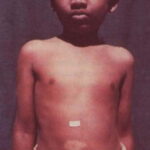

Patients with vitiligo present with one to several amelanotic macules that appear chalk- or milk-white in color. The lesions are usually well-demarcated, but the margins may be scalloped. They are accentuated on Wood's lamp examination. Lesions enlarge centrifugally at an unpredictable rate and can appear on any body site, including mucous membranes. However, initial lesions occur most frequently on the hands, forearms, feet, and face. When vitiligo occurs on the face, it often favors a perioral and periocular distribution.

Depending on ethnic color, vitiligo is more or less conspicuous .